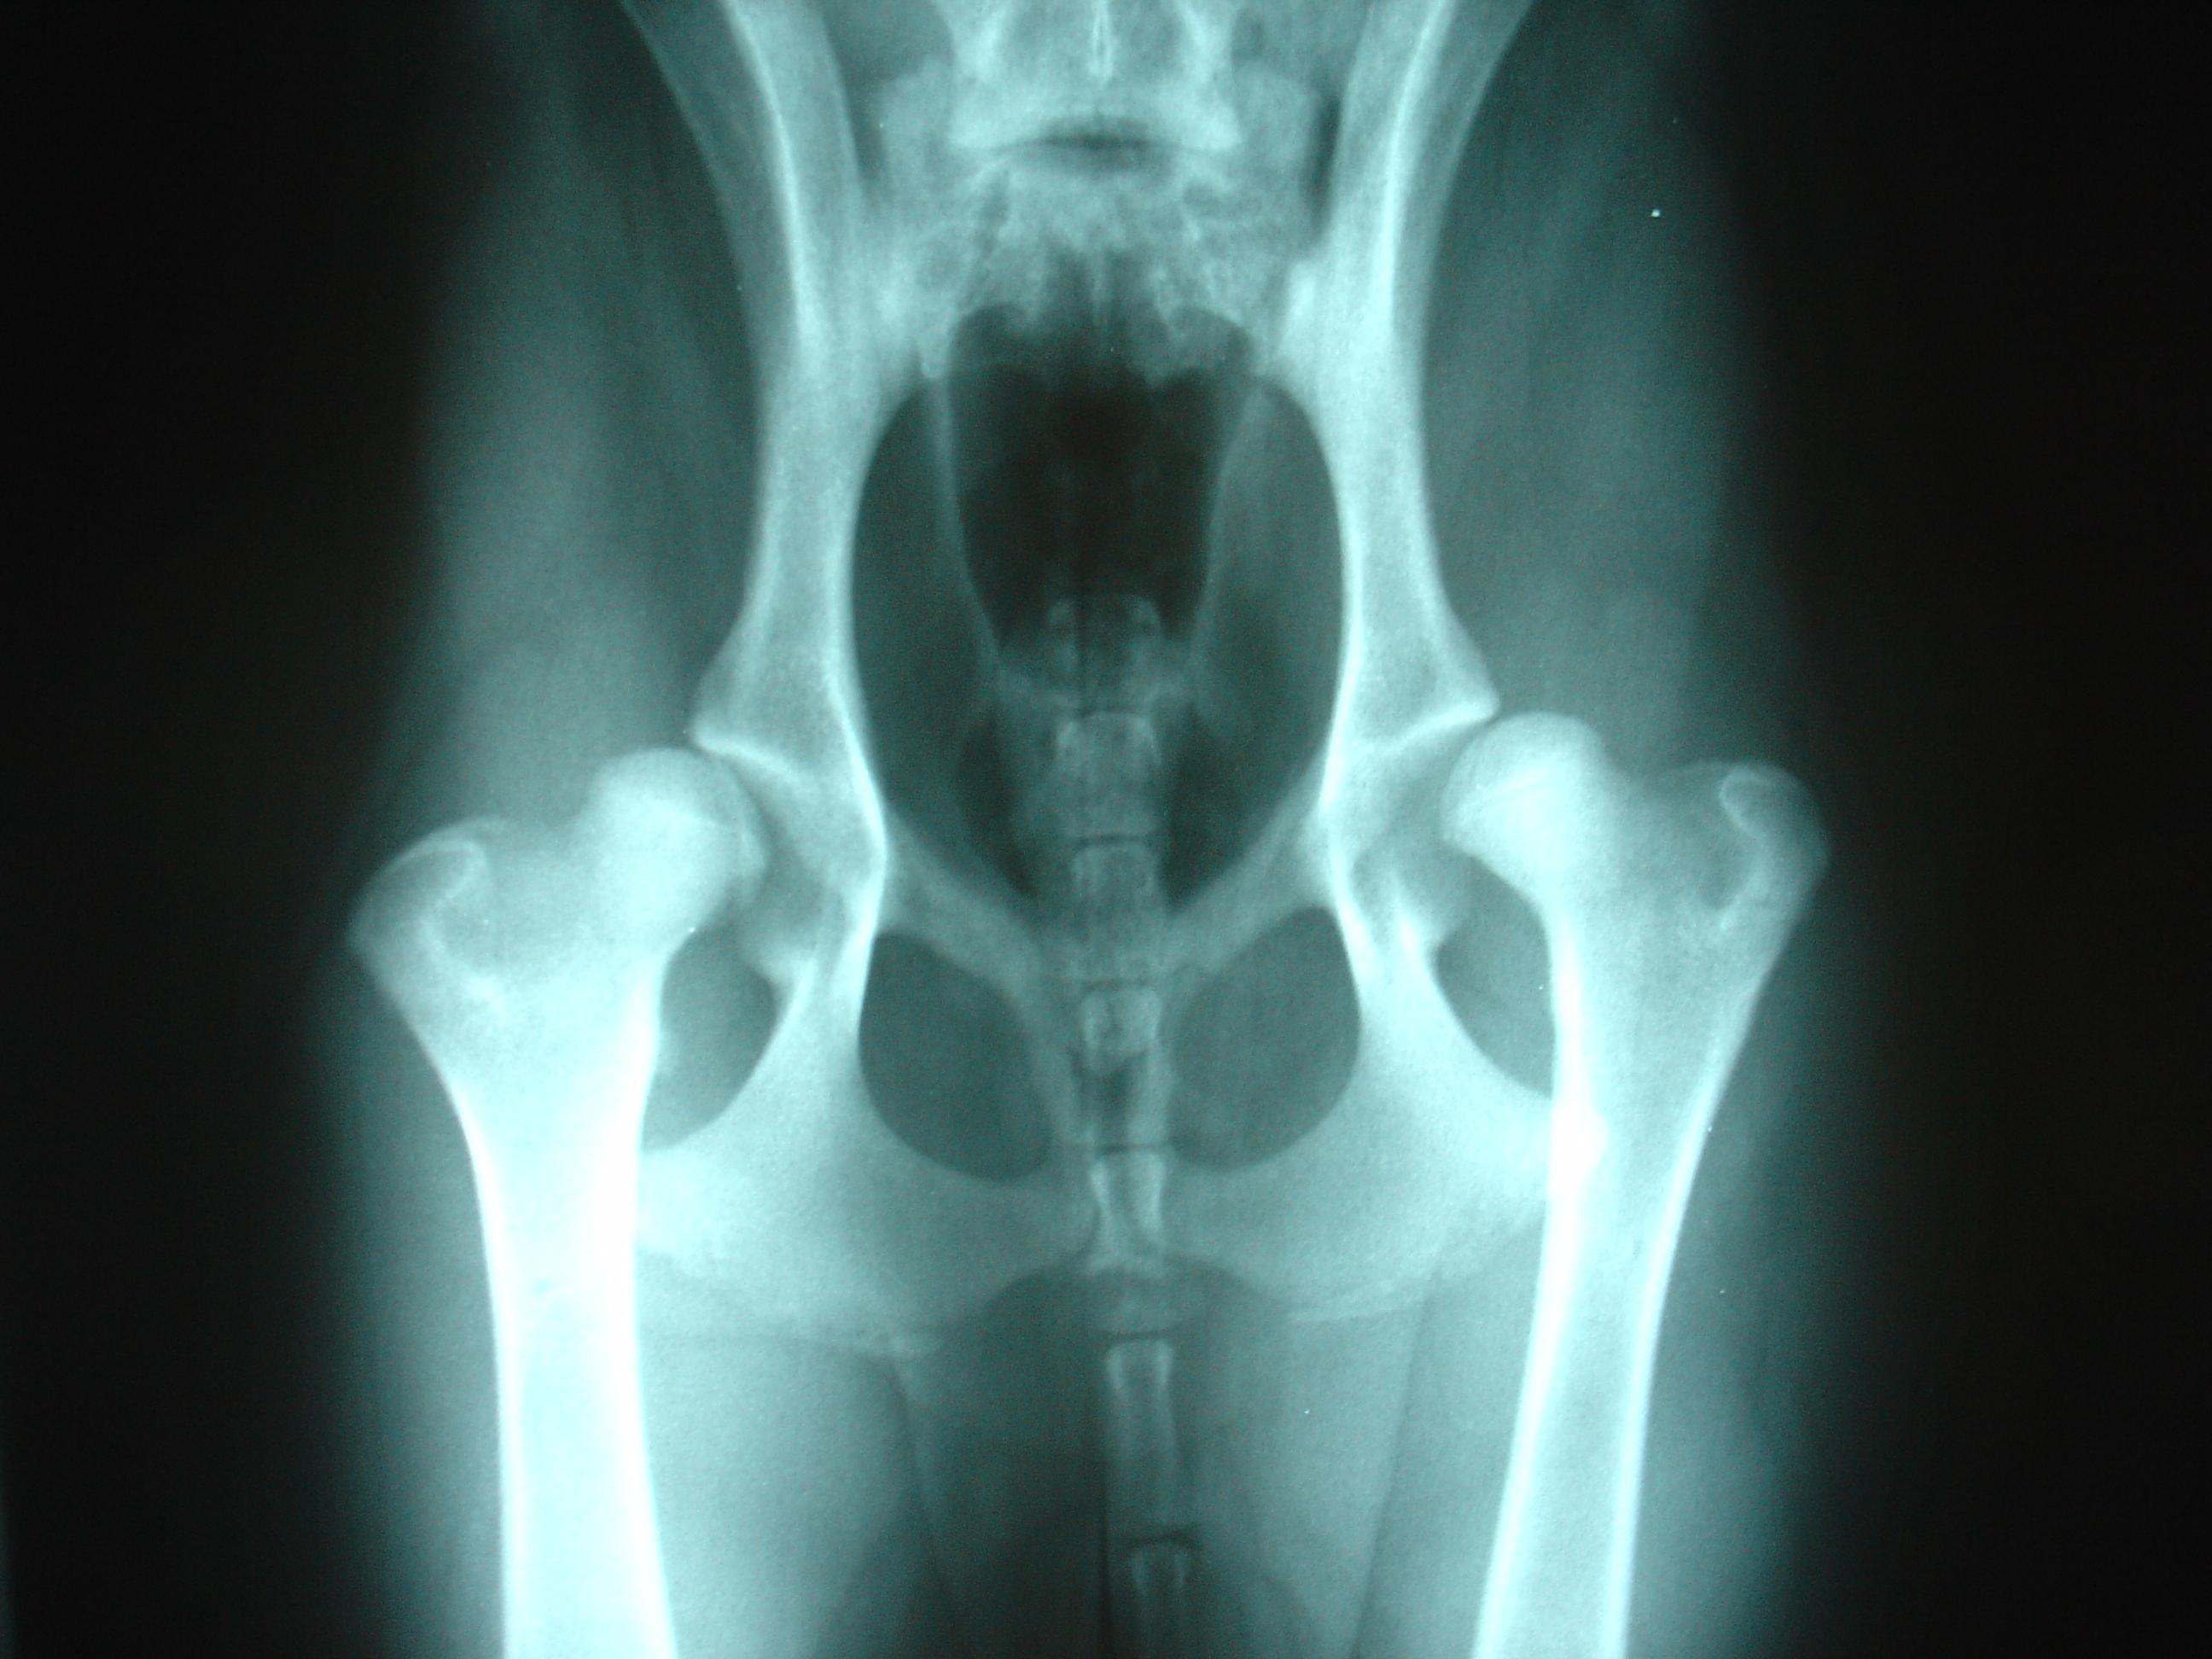

Sin lugar a dudas, la región más sensible de su cuerpo son el abdomen y las extremidades, ya que el pastor alemán es una de las razas caninas más propensas a desarrollar displasia de cadera y de codo. No obstante, también existen otras enfermedades comunes en el pastor alemán, tales como: